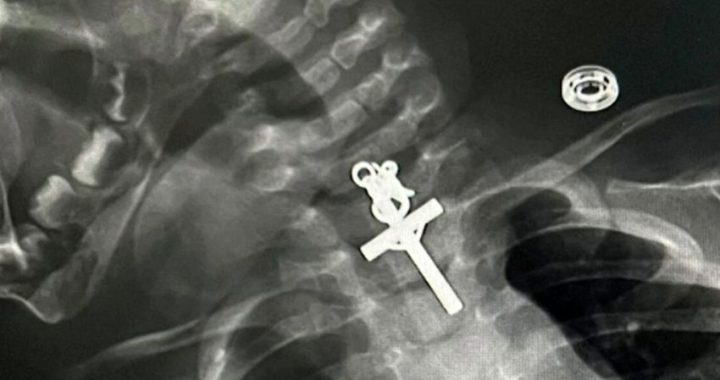

L’incredibile scoperta dopo la radiografia

La bimba è stata portata all’ospedale Victor Lazarte Echegaray, a La Libertad in Perù, dove i medici in seguito ad una radiografia hanno fatto la scioccante scoperta: la piccola aveva ingoiato un crocifisso. Tuttavia, come ha spiegato il gastroenterologo Luis Alberto Esteves Cabanillas, hanno dovuto aspettare per procedere all’intervento che si è rivelato molto complesso: “La bambina ha ingoiato un crocifisso, abbiamo dovuto aspettare 6 ore perché lo stomaco fosse vuoto poiché aveva bevuto il latte. Successivamente è stato effettuato il complesso intervento e tutto è andato molto bene. Questo grazie ai grandi professionisti di cui disponiamo”.

La piccola ha subito un intervento di endoscopia per rimuovere il crocifisso e l’operazione si è rivelata ancora più complessa di quanto non lo fosse già poiché l’oggetto era incastrato e quindi c’era il serio rischio di provocare dei danni.